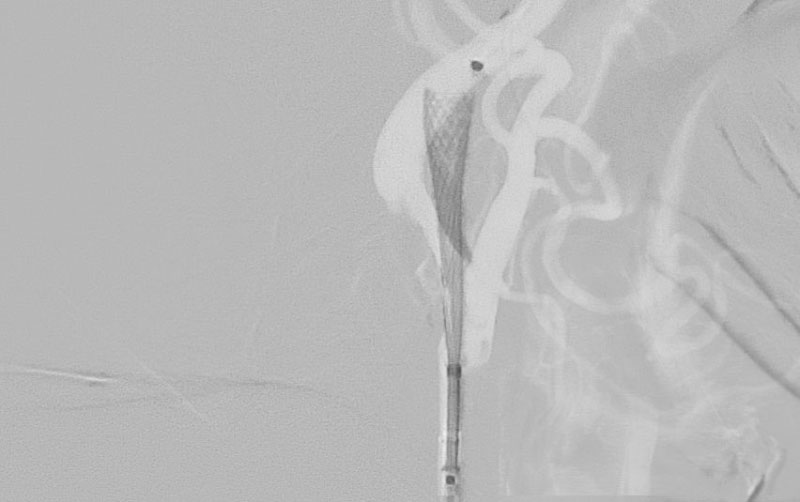

1357

'23年3月10日

左頚部内頚動脈狭窄症

80代

大阪府の病院

中

治療